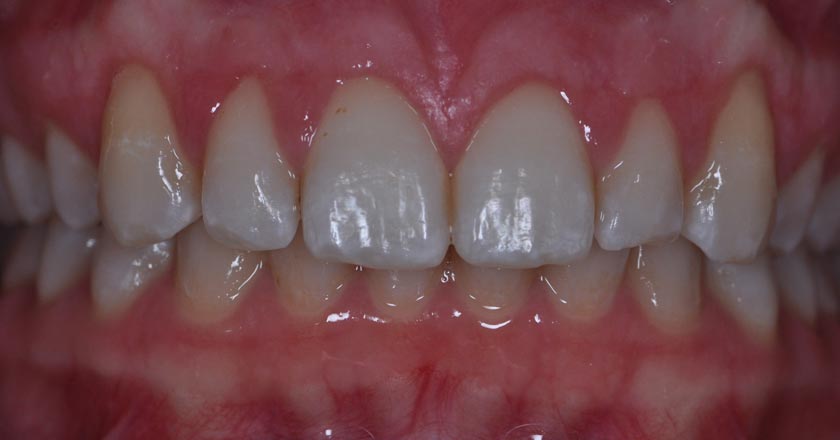

Gum Graft Lower - Before And After

Gum Graft Upper - Before And After